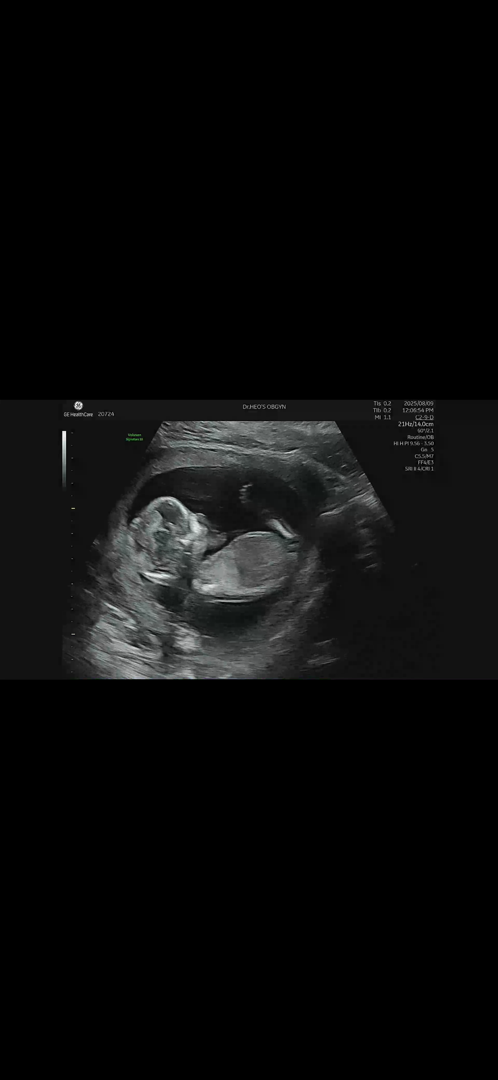

13주 5일 각도법 봐주세요 :)

각도법 고수님들 아들일까요 딸일까요 :)